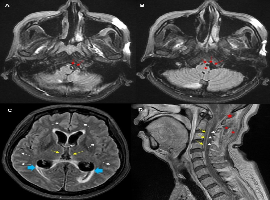

Citation: Soo-Hyun Park, Woo Chang Chun, et al. Fatal Central Nerve System Infection After Acupuncture Through the Extra-Axial Space of the Cervicomedullary Junction. Clin Image Case Rep J. 2021; 3(2): 136.